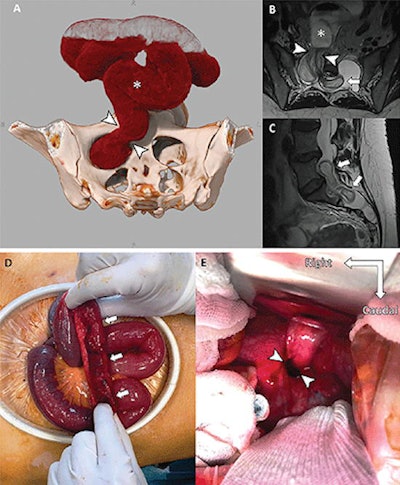

The 2022 winner was from an article published on 14 June 2022, titled, "Intradural Small Bowel Herniation." by neuroradiologists at the Francois Mitterrand University Hospital in Dijon, France. The cinematic 3D-rendered image depicts unusual pathology in a case of a 38-year-old woman with Marfan syndrome who underwent resection for a presumed right ovarian cyst.

Images of a 38-year-old woman with Marfan syndrome who was diagnosed with intradural small bowel herniation through a torn right S1 dural ectasia. (A) Oblique global illumination rendering of abdominal CT scan after semiautomatic segmentation of the enlarged afferent small bowel (*). The hernia orifice (arrowheads) separates the peritoneal cavity and the intradural space. (B, C) T2-weighted MRI scans in (B) axial and (C) sagittal planes show the herniated loop (arrowheads in B) of small bowel (* in B) ascending at L5-S1 (arrows), causing significant compression of the adjacent cauda equina nerve roots. All figures courtesy of Radiology.The first runner-up is an article published on 3 August 2021, titled, "Myocarditis Following COVID-19 Vaccination," by a group at University Hospital Bonn, Germany. This is the third consecutive year in which a COVID-related image was honored among top contenders.